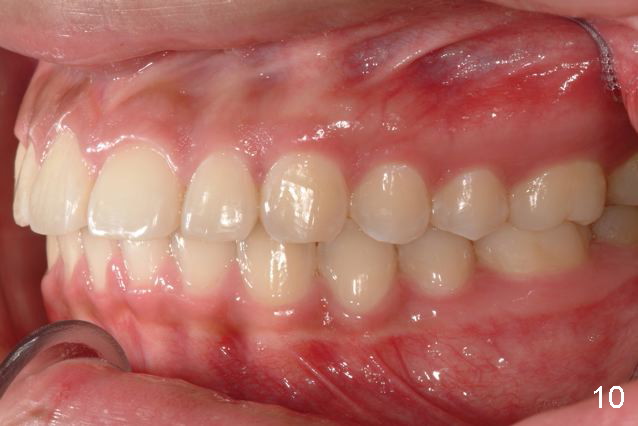

Answer: I was afraid tooth #8 would try to rotate (Fig.).  I do not like U bonded retainers as much as lower but I thought maybe in this case due to #8 initial position.  I have provided 2 removable retainers to fit over for insurance!

Excellent thinking.  According to the final photos, you must have done something to overcorrect the rotation of the two centrals.  Did you do it with purpose or by accident?  How did you do it, although Amy may not like it.  It seems to me that there is no practical way to overcorrect rotation.

By the way, her parents like the result so much that they even feel that their future grandchildren will not have crowding like them.  Good copy from Amy, not bad copy from them.  Anyway, good result and you will get more cases if you can practice forever.  I am afraid that you should be able to, at least having gut/will to do so.